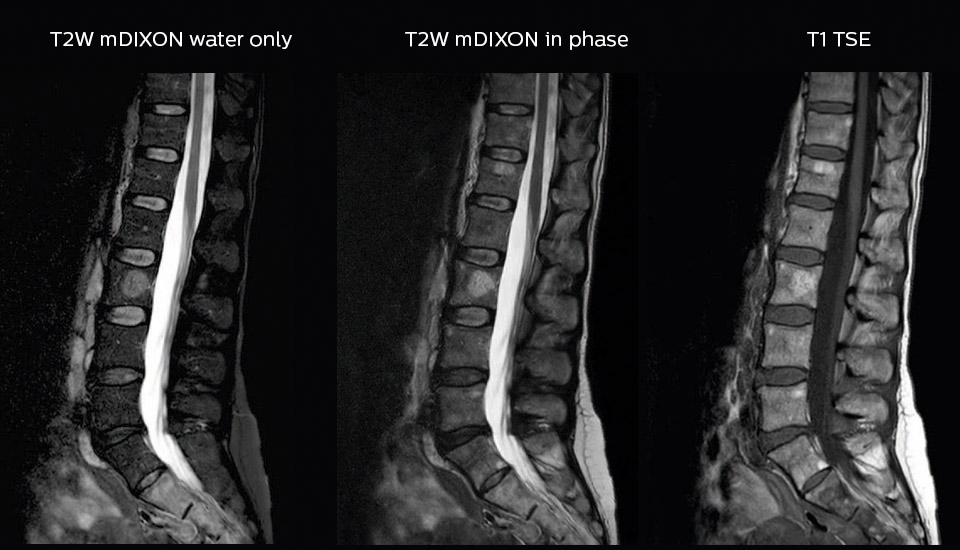

“In our lumbar spine MRI, the value of mDIXON TSE is so obvious. Normally we perform T1 and T2 scans in sagittal and transverse orientation.It used to take too much time to add a sagittal T2 with good fat suppression.But now, using mDIXON TSE, we get the sagittal T2 fat suppressed images ‘for free’, that is: without adding time.” “Diagnostically that is a great benefit. I sometimes see abnormalities in the fat suppressed sagittal T2 that would be quite challenging to notice in the T2 without fat suppression. There have been several diagnoses that I could make easier because of our exam setup with mDIXON TSE, such as sacrum insufficiency fractures and sacroileitis; these were more challenging with our previous exam setup.”

Dr. Heggelman raves about mDIXON TSE because it provides him an extra image series without having to add another scan. “With mDIXON TSE, we not only get a T2-weighted series, but we also get the T2 fat suppressed images ‘for free’ in the same scan. I feel much more confident with the homogeneous fat suppression that mDIXON TSE provides under virtually all conditions, even in this challenging anatomy. SPAIR and SPIR weren’t good enough due to the susceptibility problems in the air cavities, so that fat suppression was not homogeneous over the whole field of view. That made it difficult to see whether something was enhancing or the fat suppression was not good enough.”

“To me the most remarkable fact is that mDIXON TSE provides us T2-weighted images with and without fat suppression at the same time. In the past we needed two separate sequences for that, so it does save some time.”